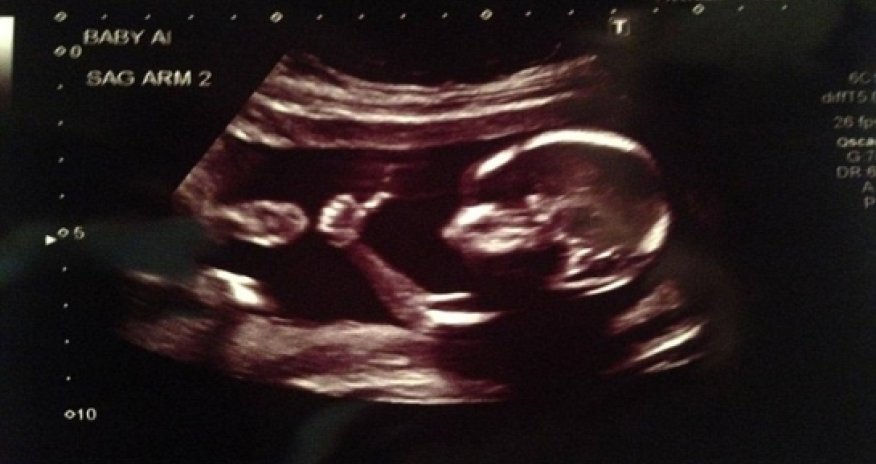

Is this the coolest baby ever?

When going for an ultrasound, parents usually rely on their doctor to tell them everything is fine.

But one couple got the message straight from their baby after the fetus was pictured giving a 'thumbs up' inside the womb.Father Brandon Hopkins posted the ultrasound picture on his Facebook page a few days ago, but when his brother shared the image on message board Reddit, it went viral.Mr Hopkins told HLN-TV: 'My brother called me and said "Your babies are famous!"' He has now revealed that his partner is expecting twins with a due date in January, and that the couple will be finding out the sex of the baby soon.The images was posted to Reddit on August 28 by a user named 'meancloth' along with the message 'ultrasound looks good'. Reddit users quickly branded the child 'Fonzie fetus' after Happy Days character The Fonz, and his famous thumbs up gesture.(dailymail.co.uk)Bakudaily.Az